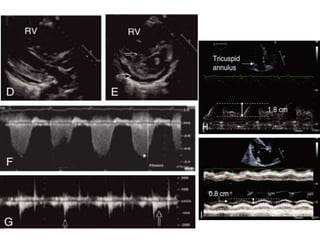

3 Two-dimensional transthoracic echocardiography- This method

estimates PASP by Doppler interrogation of a tricuspid regurgitant jet

and does not determine right atrial pressure, PVR, or PAWP accurately,

all of which are important for assessing PH clinically.

• In one-third of patients with proven PH, a sufficient tricuspid jet is

lacking and PASP is unmeasurable. Thus, echocardiography alone is

insufficient for diagnosing, classifying, and fully prognosticating

patients

• Decreased pulmonary vascular distensibility results in the formation

of a “notch” in the RV outflow tract Doppler envelope as well as

decreased pulmonary artery acceleration time. When these are

observed in the setting of a normal left atrial dimension, increased

PVR greater than 3.0 WU may be present.

• Other RV functional measures-(TAPSE, longitudinal myocardial

velocity (S’), fractional area change (FAC), Tei index speckle tracking,

and ejection fraction by three-dimensional echocardiography.